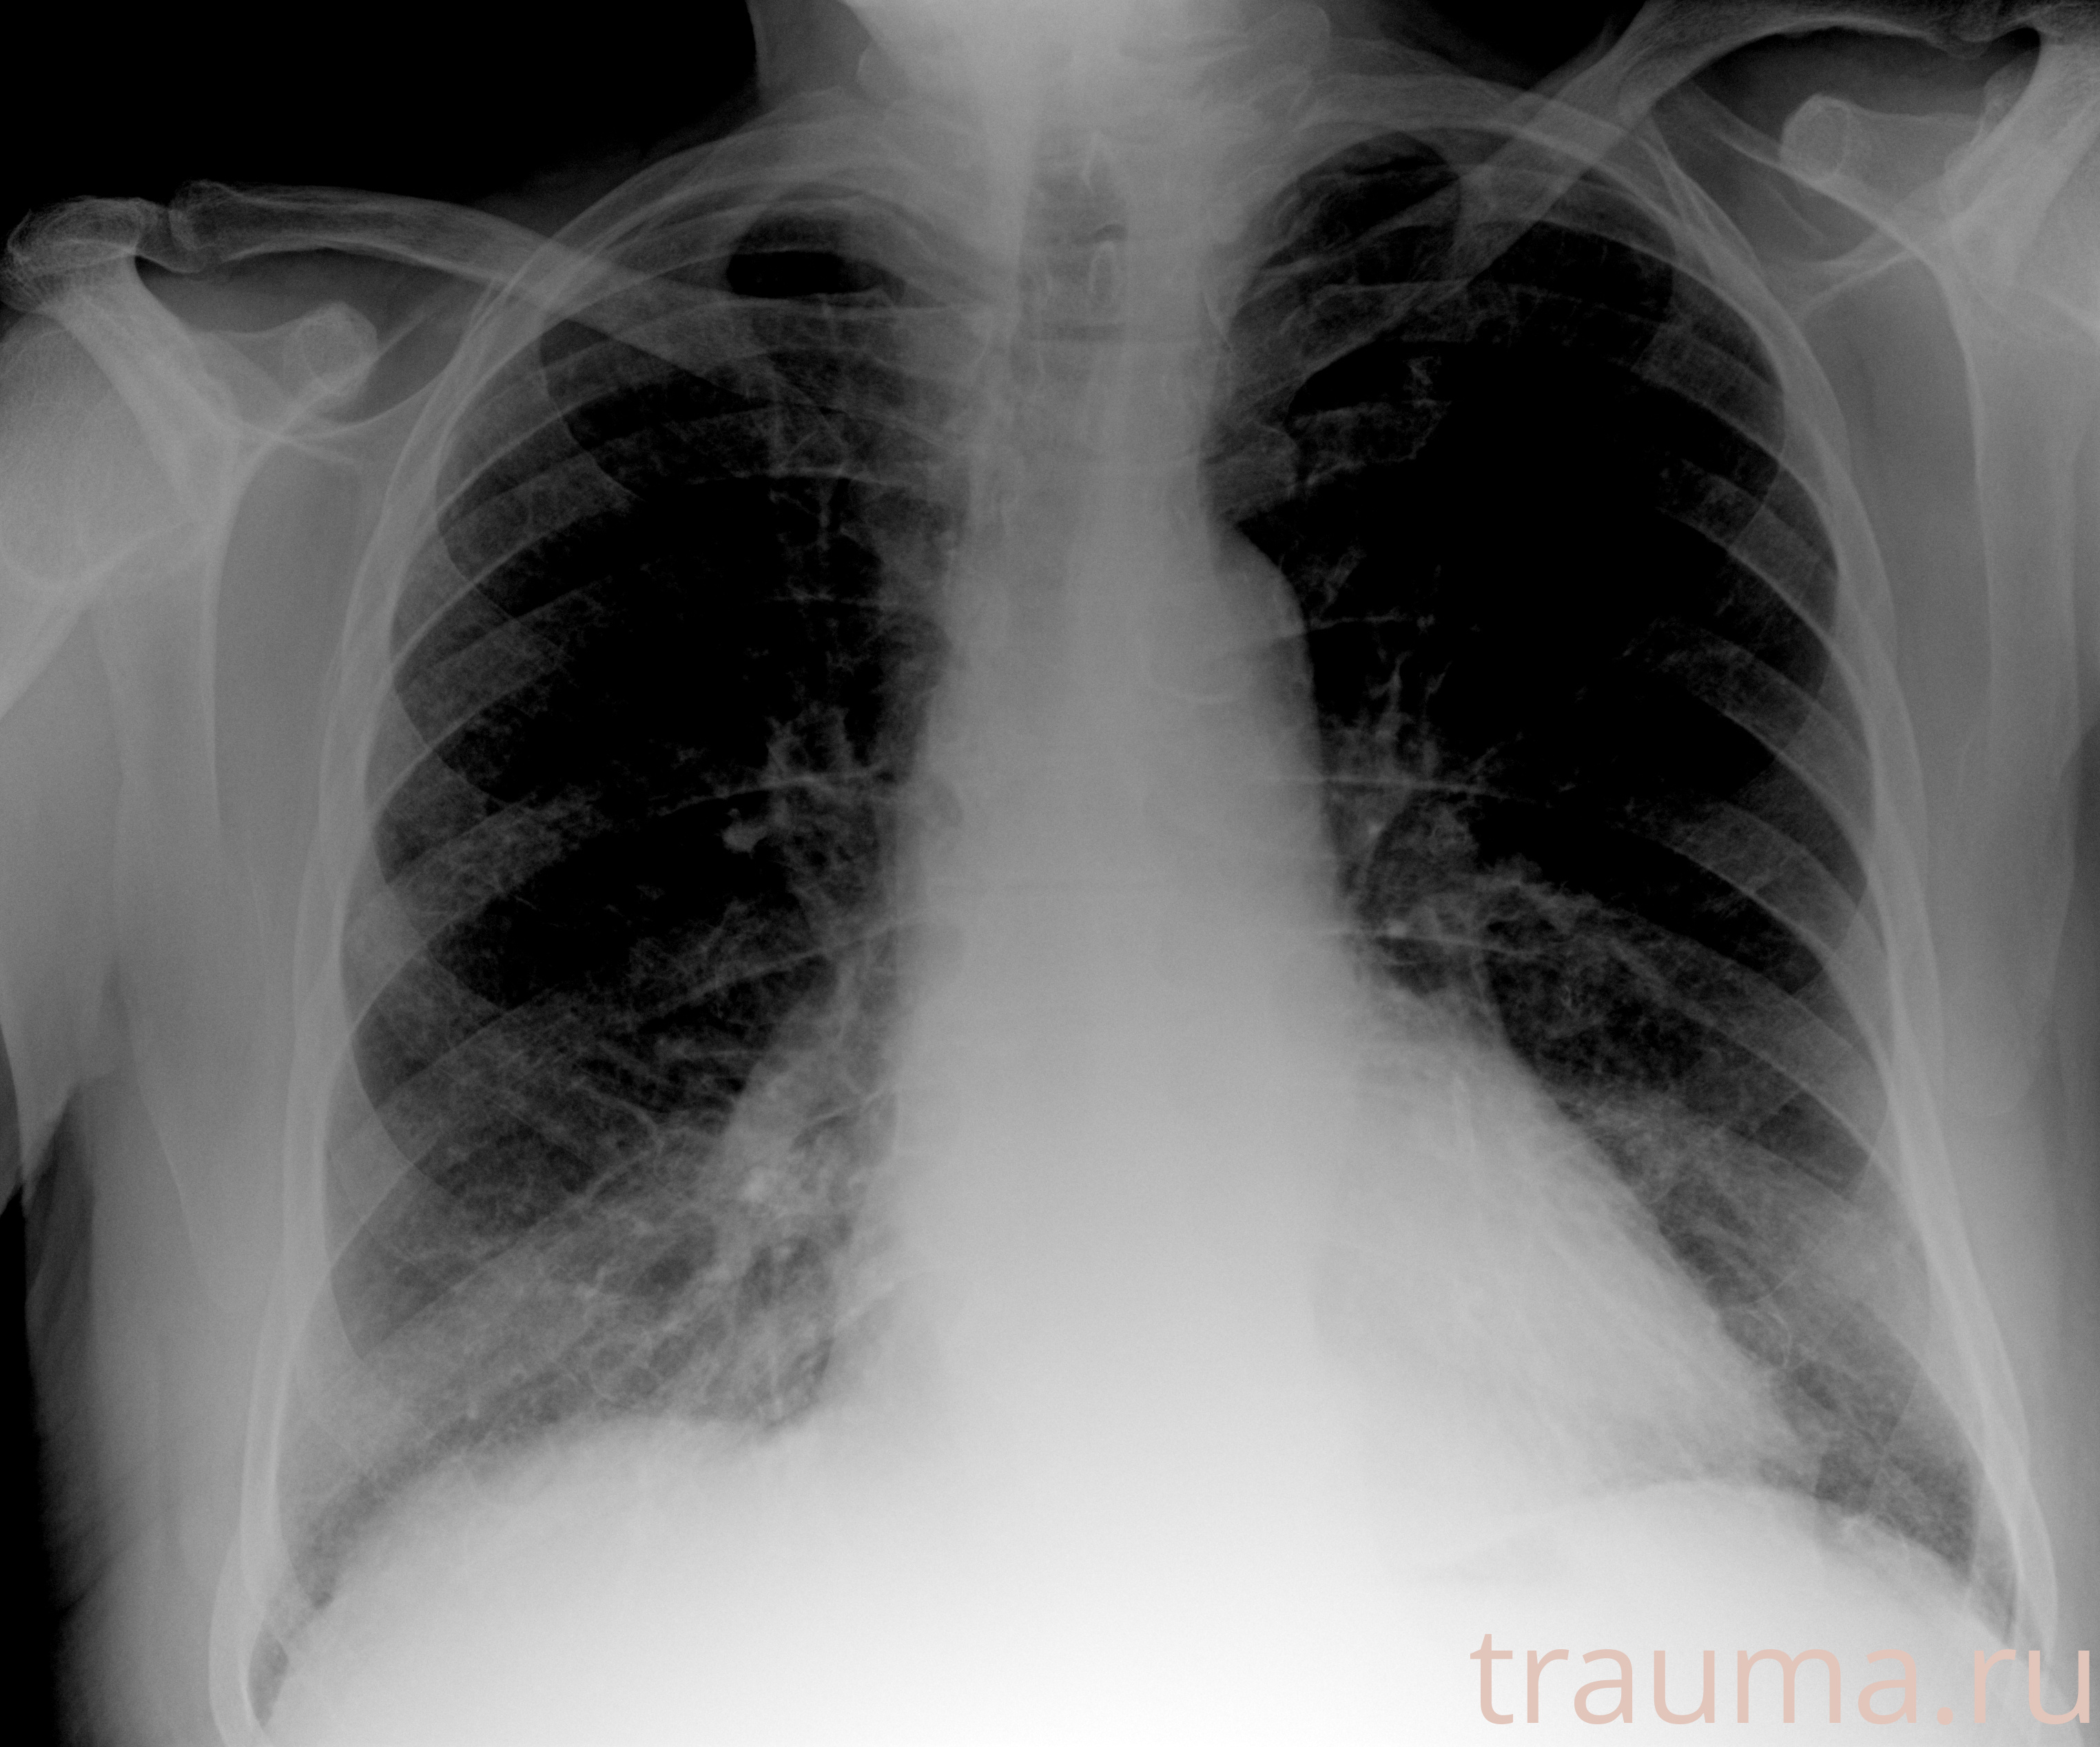

Рентгенограммы

Рентген на дому: по вашему адресу приезжает врач-рентгенолог, травматолог-ортопед с мобильным рентгеновским аппаратом, проводит диагностику травмы или заболевания, делает необходимые рентгенограммы, дает рекомендации по дальнейшему лечению. Получить качественные снимки в домашних условиях возможно благодаря уникальной методике, разработанной МосРентген Центром для института  Склифосовского

Яркость: 1   Контраст: 1   Инвертировать: 0 Увеличение: 1

Перетаскивайте мышь вверх/вниз для контраста, влево/право для яркости. Прокрутка колесом изменяет масштаб. Нажмите Сбросить для возврата к исходному изображению. При увеличении держите мышь в той области, которую хотите рассмотреть.